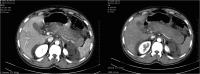

Dengue fever is a mosquito-borne arthropod-borne viral (arboviral) tropical disease in humans affecting 50-528 million people worldwide. The acute abdominal complications of dengue fever are acute appendicitis, acute pancreatitis, acute acalculous cholecystitis and non-specific peritonitis. Acute pancreatitis with new onset diabetes in dengue shock syndrome (DSS) is very rarely reported. We describe a case of 30-year-old man admitted in intensive care unit and was diagnosed with DSS with RT-PCR, NS1 antigen and dengue IgM antibody being positive. Abdominal ultrasound and computerized tomography confirmed acute pancreatitis. Patient required insulin after recovery. Diabetes mellitus caused by DSS is under-reported and lack of awareness may increase mortality and morbidity.